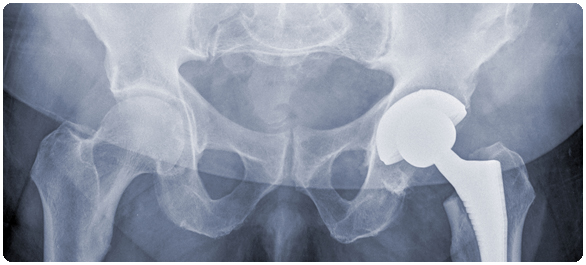

สะโพกหัก โรคฮิตของคนแก่ (ตอนที่ 2)

สะโพกหักทำให้การพึ่งพาตัวเองทำได้น้อยลงและบางครั้งทำให้ชีวิตสั้นลงด้วย ประมาณครึ่งหนึ่งของคนที่สะโพกหักจะไม่สามารถพึ่งตัวเองได้ ซึ่งหากมีผลทำให้ไม่สามารถเคลื่อนไหวได้เป็นระยะเวลานาน ก็อาจทำให้เกิดโรคแทรกซ้อนได้ดังนี้